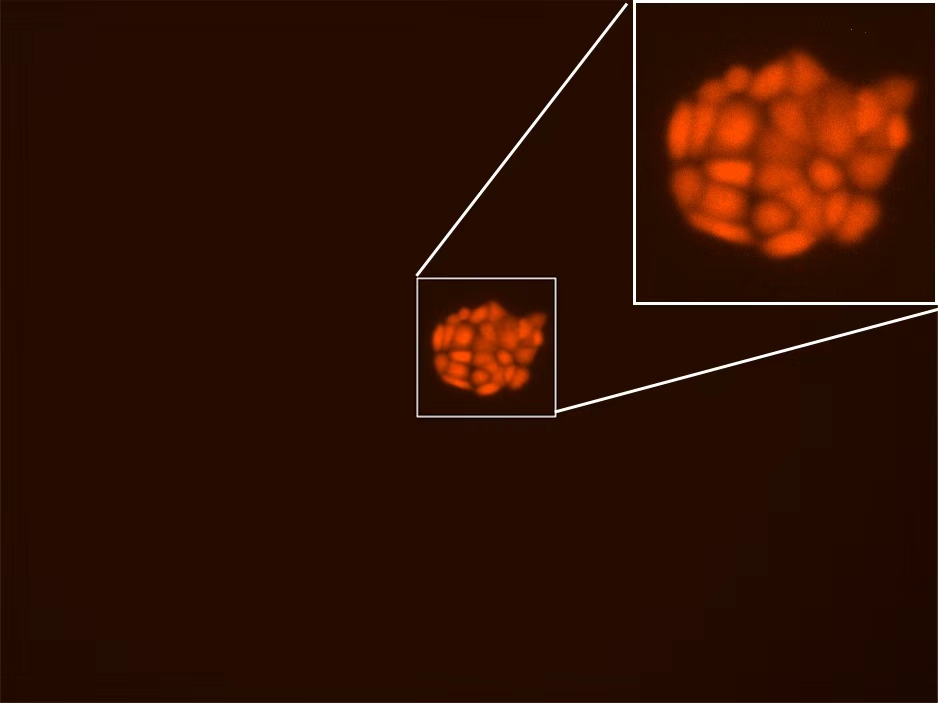

生拓生物是一家专注于为生物医学基础研究提供高效、优质解决方案的服务提供商。我们致力于通过专业、可靠的产品与服务,加速科研探索进程,助力生命科学领域的创新与发展。核心业务高品质生物试剂:提供涵盖分子生物学、细胞生物学、免疫学等多个领域的核心试剂,严格把控质量与稳定性,确保实验结果的可靠性与重复性。细胞系与稳转细胞株:拥有丰富的细胞资源库,包括常见肿瘤细胞系、双...